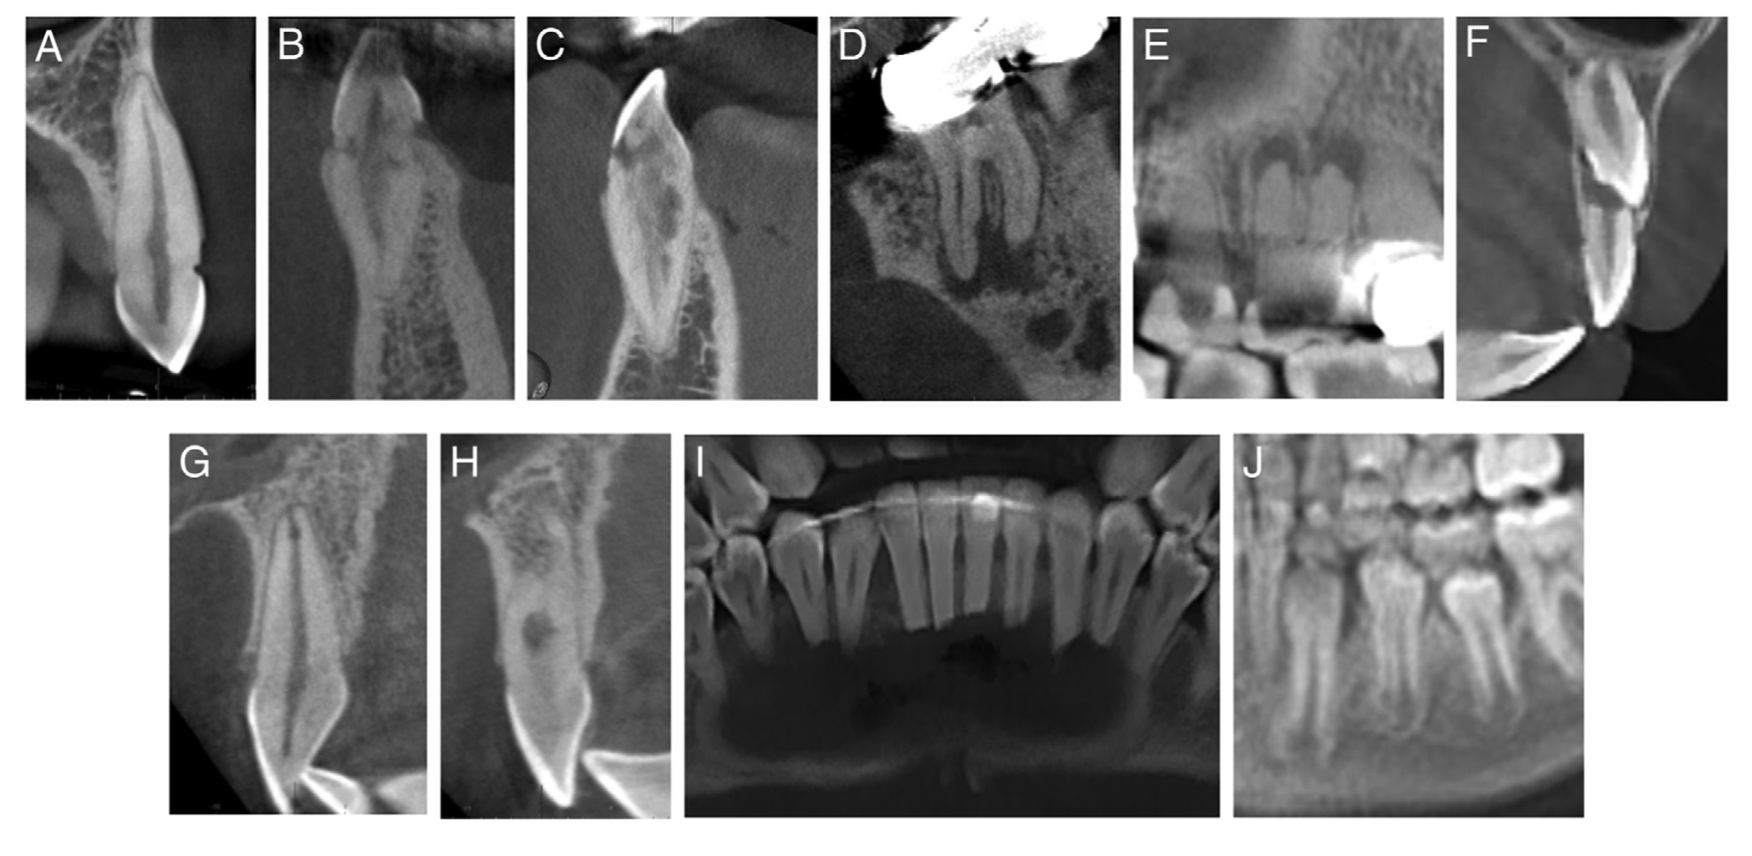

Цервикальная резорбция корня: начинается в шейной области зуба и обычно вовлекает коронковую треть корня. Отличается от наружной резорбции локализацией и инвазивным «нитевидным» распространением в дентин. (См. Рис. 1 A–C.)

Наружная воспалительная резорбция корня: характеризуется радиопрозрачными дефектами вдоль апикальной и средней третей поверхности корня, с вовлечением пульпы или без него. (См. Рис. 1D.)

Эта категория включает резорбцию, индуцированную инфекцией (апикальную воспалительную резорбцию), вызванную апикальным периодонтитом, которая может приводить к притуплению верхушки корня или расширению апикального отверстия. Зубы с апикальным периодонтитом относили к этой группе. (См. Рис. 1E.)

Резорбция, индуцированная давлением: рентгенологически определяется рядом с ретинированным зубом и по пути его прорезывания. (См. Рис. 1F.)

Внутренняя резорбция: распознаётся как одно или несколько локализованных расширений корневого канала; может распространяться до поверхности корня и вызывать перфорацию или не распространяться. (См. Рис. 1G.)

Заместительная резорбция: подразумевается, когда резорбтивный дефект заполнен костью; рентгенологически проявляется исчезновением периодонтальной щели и компактной пластинки, с локальным сращением зуба с костью. (См. Рис. 1H.)

Резорбция корня неодонтогенного происхождения. (См. Рис. 1I.)

Физиологическая резорбция: рентгенологические признаки утраты корня молочного зуба рядом с постоянным зубом-преемником. (См. Рис. 1J.)

Рисунок 1. Типы резорбции корня

Типы резорбции корня: A–C — цервикальная резорбция корня с демонстрацией нарастающей тяжести; D — наружная воспалительная резорбция корня; E — апикальная резорбция, индуцированная инфекцией; F — резорбция, индуцированная давлением; G — внутренняя резорбция; H — внутренняя и заместительная резорбция; I — резорбция корня неодонтогенного происхождения; J — физиологическая резорбция корня.